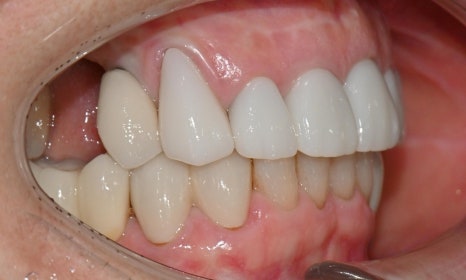

2026.2 치료 마무리 후 사진 - 연세정원치과

이와 같이 임시치아 단계에서 충분히 디자인을 조정하고 상담을 마무리하면, 기공소에 보다 정확한 디자인을 전달할 수 있어 최종 보철 만족도가 크게 높아집니다. 웃을 때나 말할 때 앞니 보철이 보이고, 아래 앞니도 추후 보철 예정이시라서 보철 색상은 다른 보철에 맞추기보다, 환자가 원하는 정도로 밝게 제작하였습니다.

치료 마무리 후 smile 사진 - 연세정원치과

앞니 보철 치료는 단순히 크라운을 새로 만드는 치료가 아니라, 잇몸 상태, 치아의 마모와 위치, 스마일라인, 발음과 식사까지 함께 고려해야 하는 종합적인 치료입니다. 특히 오래된 보철을 교체하는 경우에는 보이지 않던 문제들이 함께 발견되는 경우가 많아, 단계별 계획과 임시보철을 통한 검증 과정이 최종 치료 결과의 정확성과 안정성을 결정짓는 중요한 요소가 됩니다. 이러한 접근을 통해, 심미성과 기능을 동시에 만족시키는 치료 결과를 얻을 수 있으며, 장기적인 유지와 환자 만족도 또한 크게 향상됩니다.

이번 케이스는 임시치아 단계에서 환자분과 충분히 소통하며 디자인을 조정한 덕분에, 기능과 심미를 모두 만족시키는 방향으로 치료를 진행할 수 있었습니다. 특히 앞니는 웃을 때나 말할 때 거의 항상 보이는 부위이기 때문에, 조금만 모양이나 색이 어긋나도 인상이 크게 달라질 수 있으므로, 얼굴과 미소 전체와 조화를 이루는 보철을 만들기 위해 환자분과 충분한 소통을 통해 세밀한 디자인 조정과 단계별 검증을 시행할 수 있었습니다.